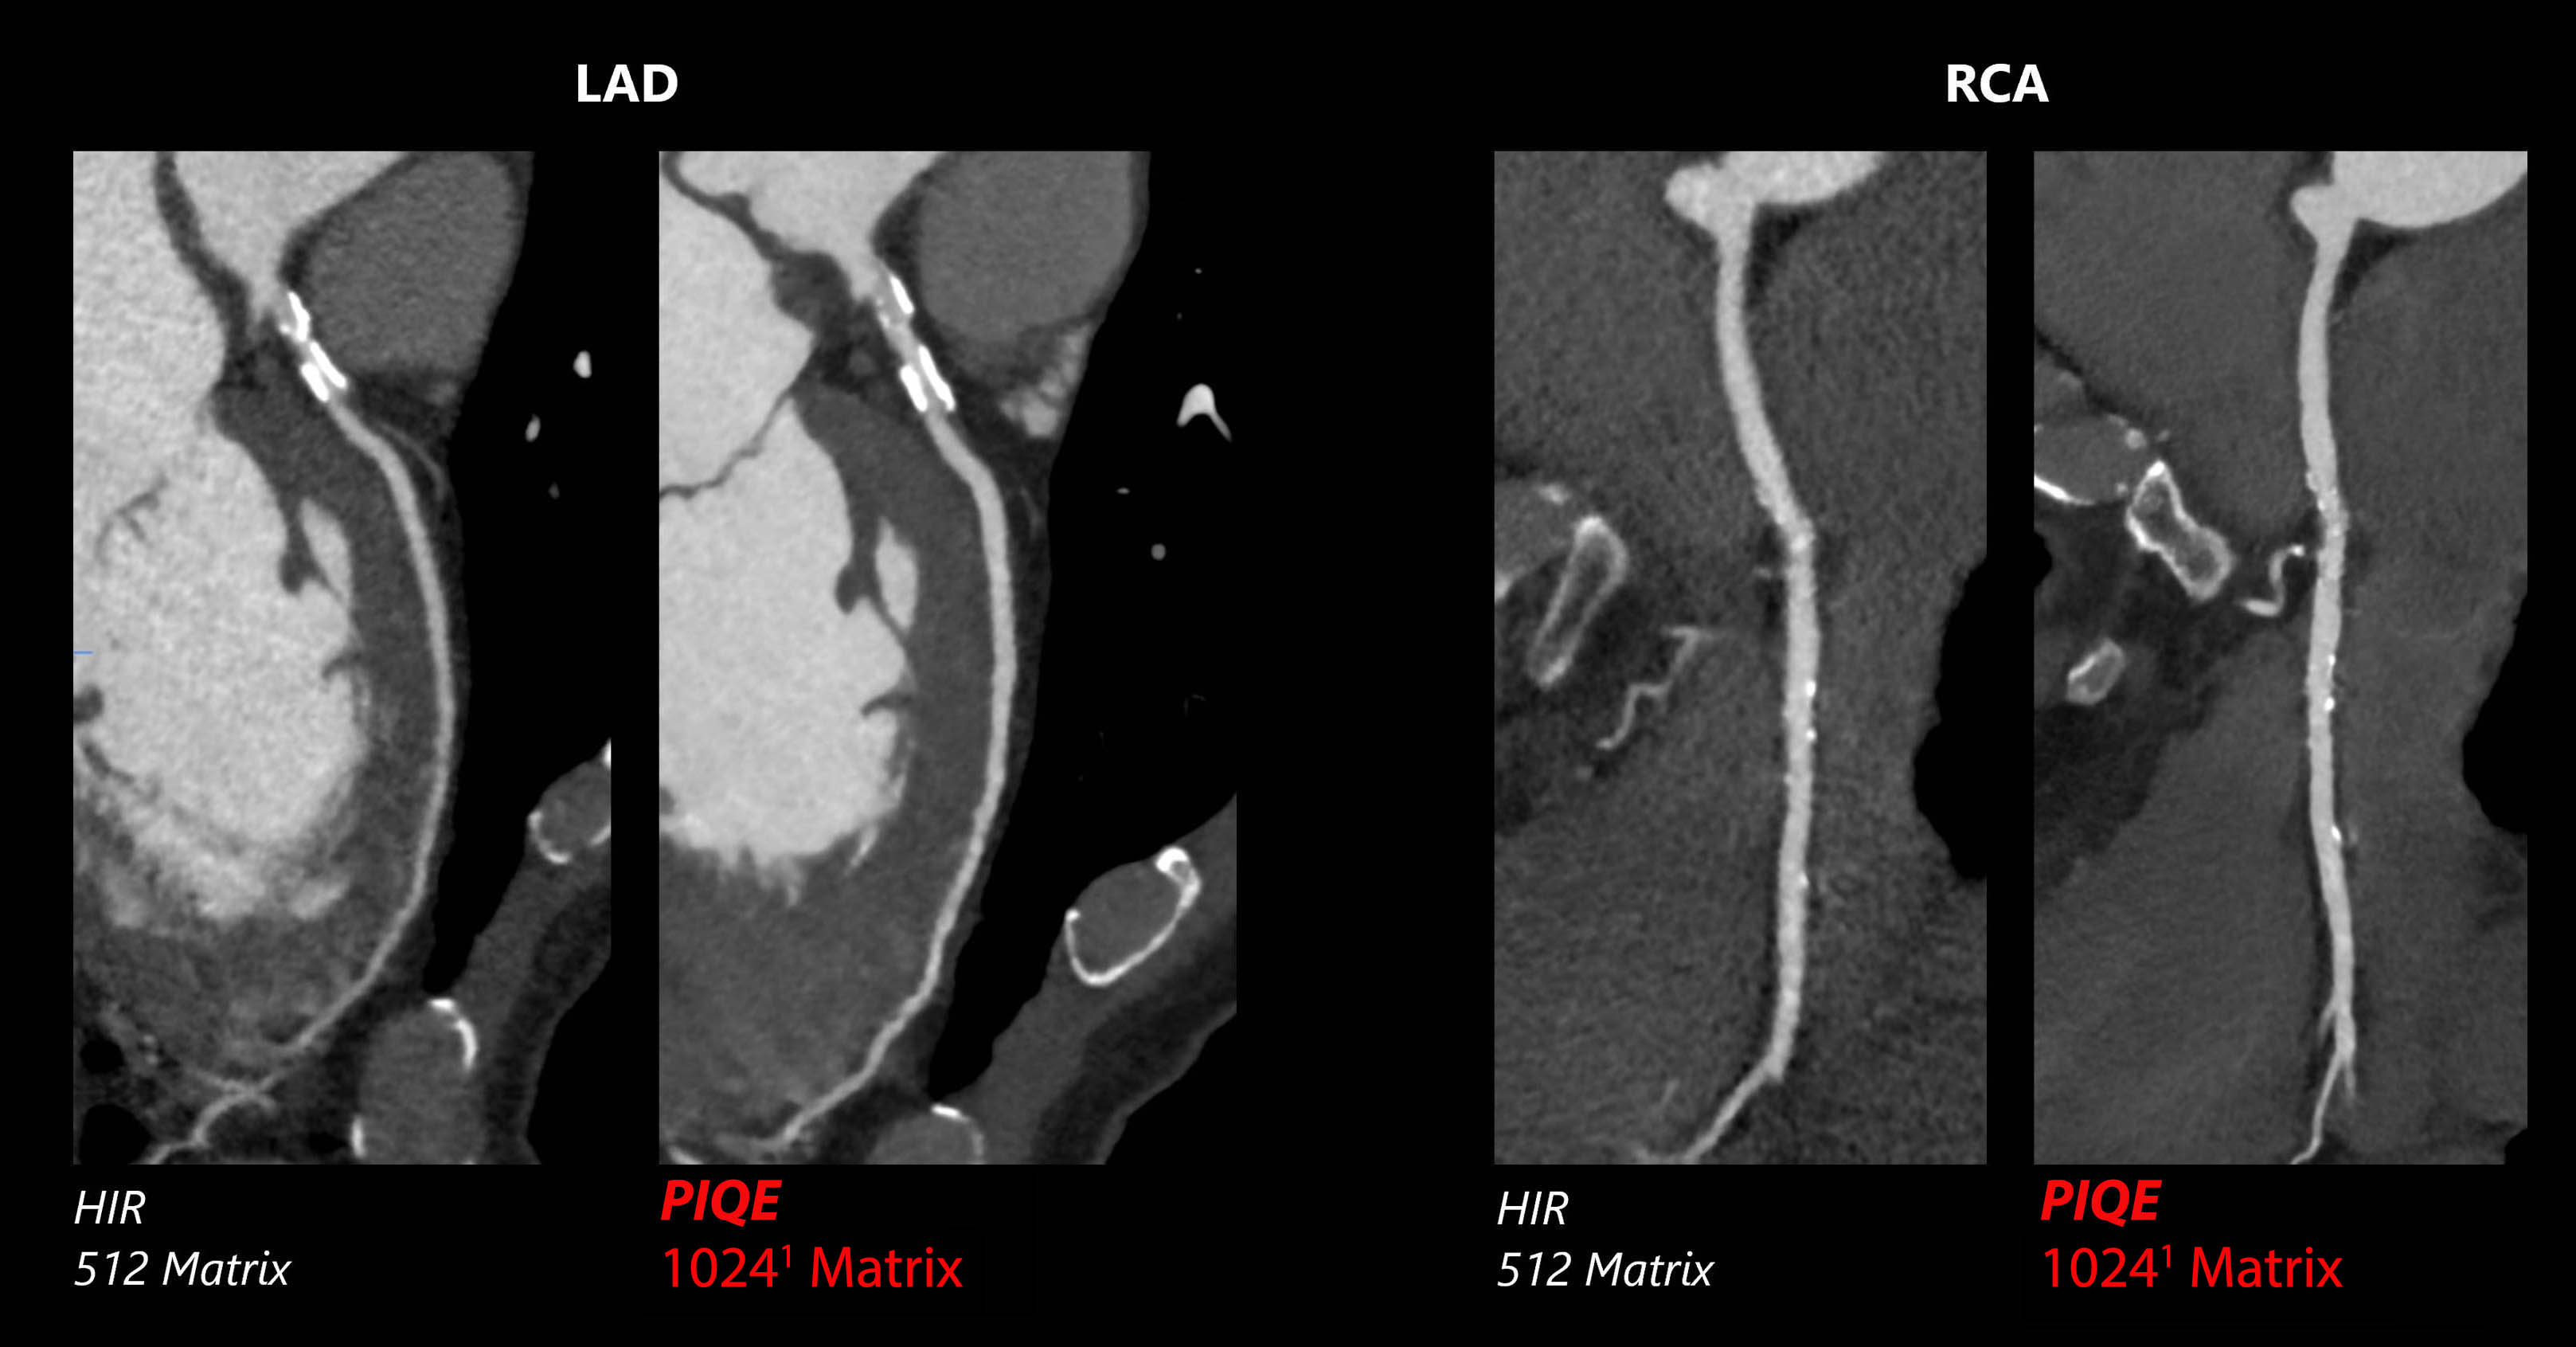

Precise IQ Engine (PIQE) 10241 DLR

Aquilion Serve SP

PIQE1 Super Resolution2 DLR improves diagnostic confidence with sharp cardiac images with improved spatial resolution.

View Scan Parameters

View Scan Parameters

| Scan Mode | kVp | mAs | Reconstruction | CTDIvol | DLP | Effective Dose† |

|---|---|---|---|---|---|---|

| Gated Helical | 120 kV | SUREExposure | PIQE | 25.6 mGy | 387.3 mGy·cm | 5.4 mSv |

† AAPM Report 96, k-factor 0.014

1 Option

Courtesy of Steinberg Diagnostic Medical Imaging, USA.